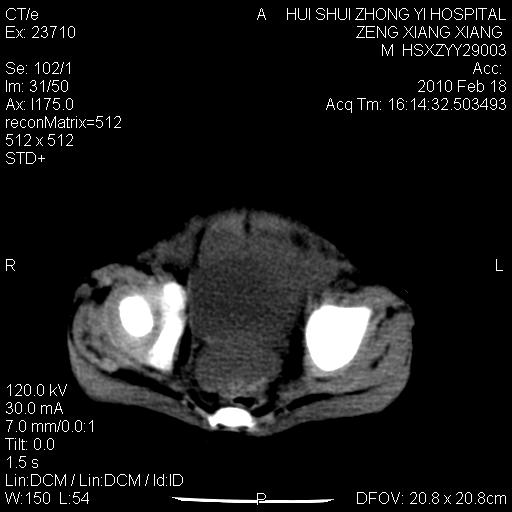

标题: PED3106:男,2岁,腹胀1月。 [打印本页]

标题: PED3106:男,2岁,腹胀1月。

定位腹膜后,肾上腺来源;

定性:恶性神经源性,肾上腺神经节母细胞瘤可能性大。

鉴别:肝母、肾母、肝脏中胚层错构瘤。

依据:年龄、有钙化,肾脏及肝脏受压移位。

肝母细胞瘤可能性大,右肾形态大体可见,不支持肾母细胞瘤,右肾移位不明显,肾上腺神经母细胞瘤可能性不大。